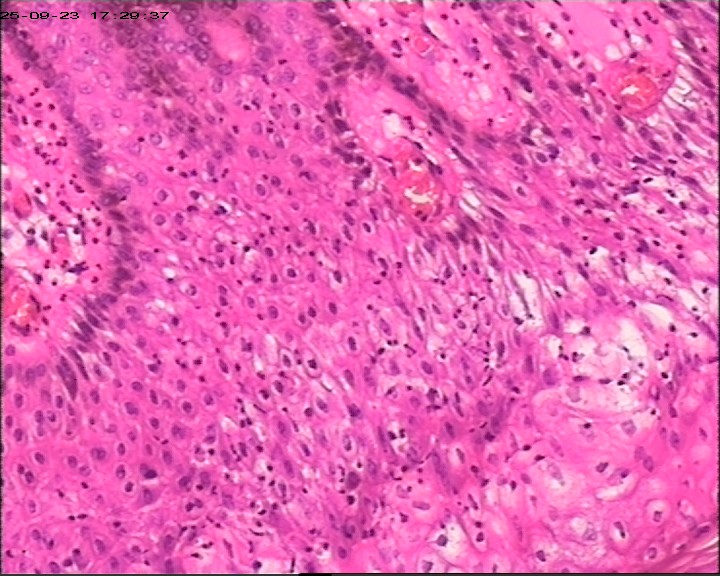

肛周脓肿组织,请帮忙看看,谢谢

肛周出血肿块伴疼痛,红肿6天。脓肿切开引流术+内痔结扎术

臀部皮肤病损

灰白灰红带皮组织3块,大小为3*2*0.5cm

鳞状上皮增生伴湿疣样改变

生炎+出血。

急、慢性炎,伴出血。